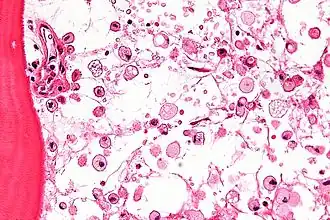

![]() На микрофотографии характерные изменения строения костного мозга при болезни Гоше — цитоплазма макрофагов напоминает смятую папиросную бумагу. Окраска гематоксилином и эозином | |